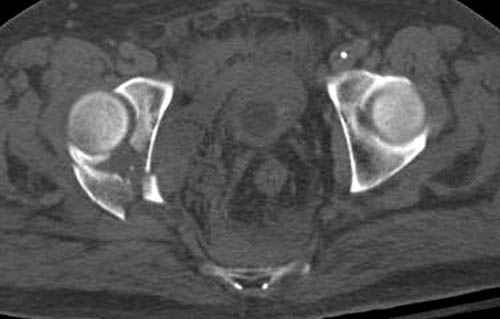

По возможности вышлите снимки, сканы таза до

реконструкции, интраоперационные.

По снимку создается впечатление о высоком поперечном переломе, задней колонны, стенки; почему не пользовались *magic screw*?

Там множество обычных 2.7 мм шурупов, потом идет фиксация основными пластинами.

Снимки здесь....